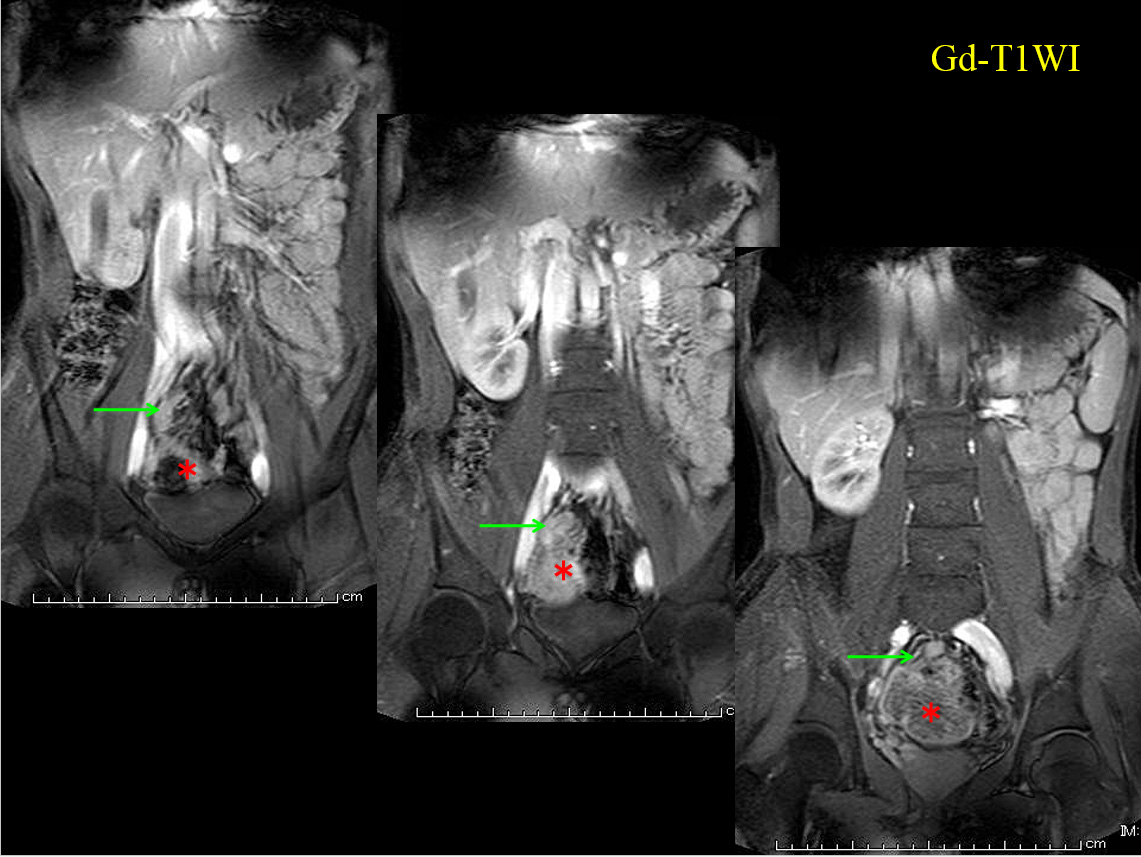

• Gd-T1WI

Gd-T1WI

MRでは、骨盤内に大きな嚢胞性病変を認める。

すなわちT2WI、T1WIでいずれも高進号を呈すが、脂肪抑制で抑制されず、造影で辺縁部のみわずかに濃染される。

内部には不均一で貯留物があると認識されるが、血性を示唆する所見には乏しい。

骨盤内の嚢胞性病変の鑑別となるが、男性であるため卵巣由来は否定的である。水平断像および冠状断像を丹念に読影すると、同病変は小腸と連続しており、腸管構造の一部であることがわかる。病変の局在は回腸末端に近く、年齢、経過を加味すると、メッケル憩室が最も考えられる。